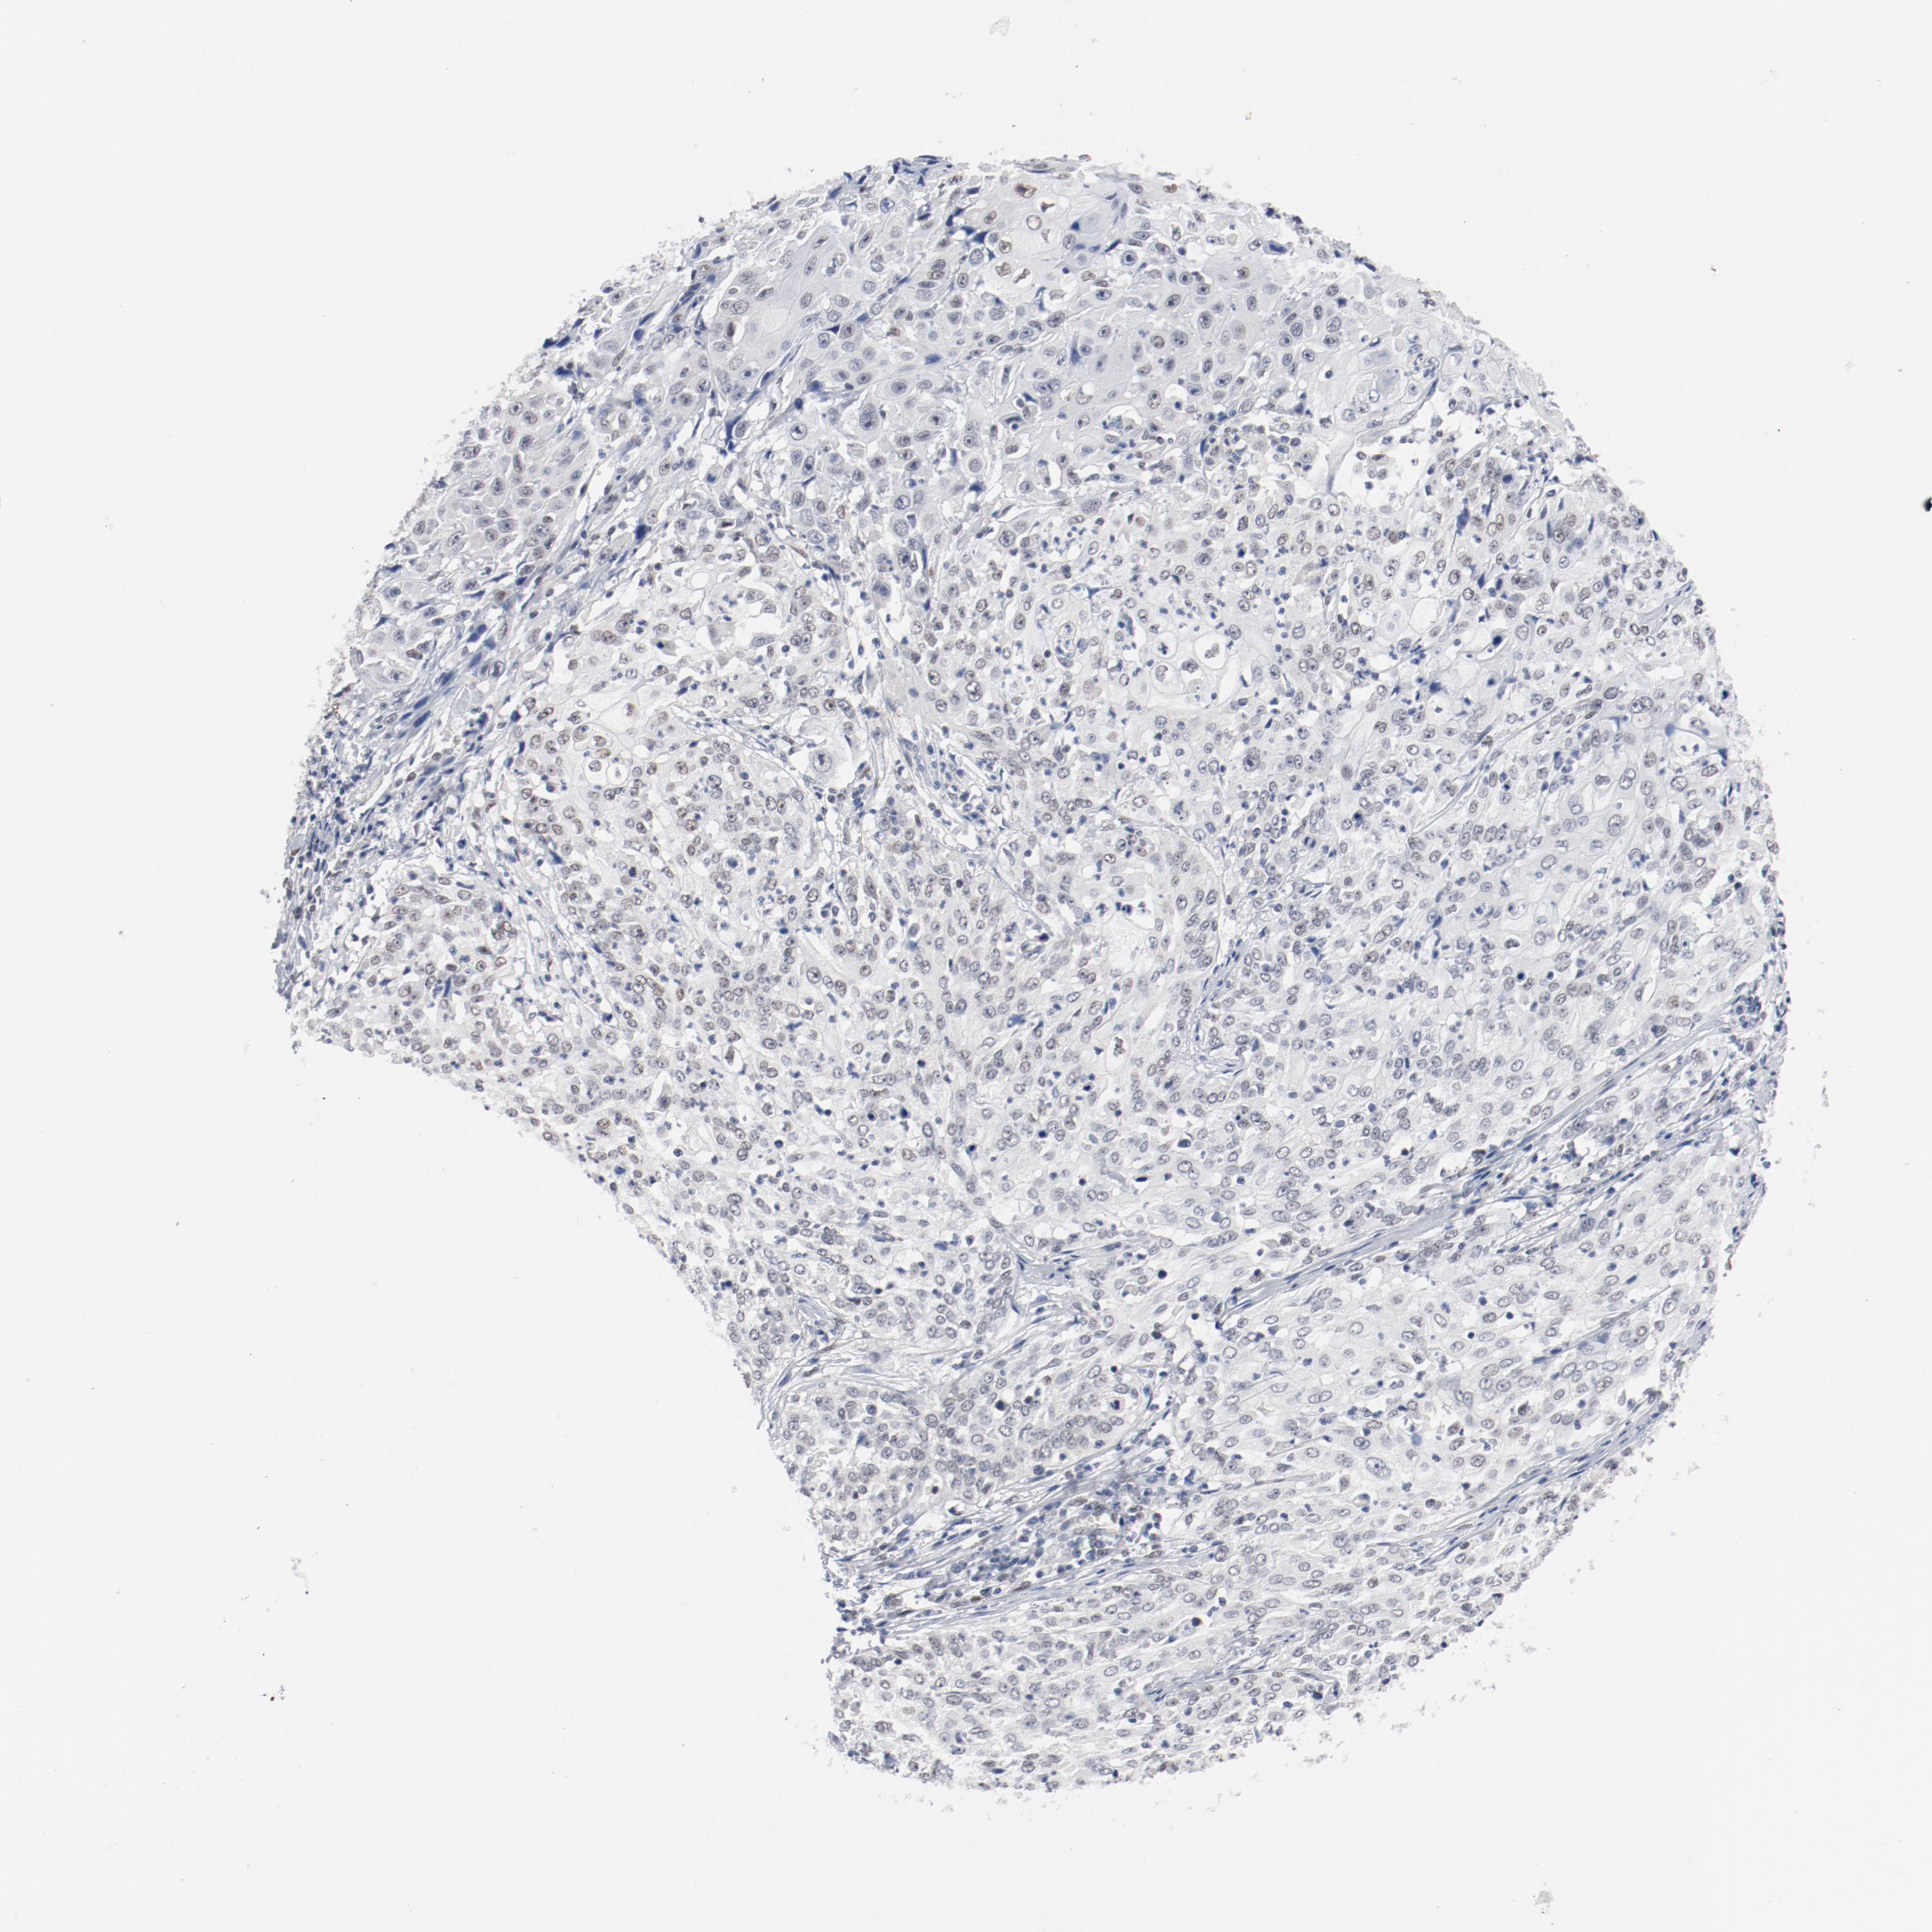

CERVICAL CANCER - Protein expressioni

A mouse-over function shows sample information and annotation data. Click on an image to view it in a full screen mode. Samples can be filtered based on level of antibody staining by selecting one or several of the following categories: high, medium, low and not detected. The assay and annotation is described here.

Note that samples used for immunohistochemistry by the Human Protein Atlas do not correspond to samples in the TCGA dataset.

Antibody stainingi

Antibody staining in the annotated cell types in the current human tissue is reported as not detected, low, medium, or high, based on conventional immunohistochemistry profiling in selected tissues. This score is based on the combination of the staining intensity and fraction of stained cells.

Each image is clickable and will lead to virtual microscopy that enables deeper exploration of all samples and also displays staining intensity scores, fraction scores and subcellular localization as well as patient and tissue information for each sample.

Antibody HPA001759

Antibody CAB004318

Staining

High

Medium

Low

Not detected

Intensity

Strong

Moderate

Weak

Negative

Quantity

>75%

75%-25%

<25%

None

Location

Nuclear

Cytoplasmic/membranous

Cytoplasmic/membranous,nuclear

Squamous cell carcinoma, NOS

Adenocarcinoma, NOS